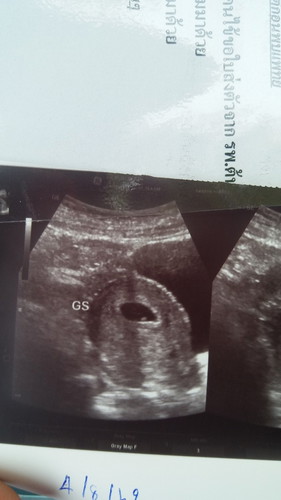

6W

เมื่อเช้าเลือดออก แม่จิตตกมาก เพราะท้องก่อนแท้งตอน8W ยังดีไปซาวด์แล้วเจอหัวใจลูก หมอบอกเห็นตัวเด็กแล้ว ฉีดยากันแท้งให้1เข็ม หวังว่าท้องนี้ จะปลอดภัยแข็งแรงไปจนคลอดน่ะลูก